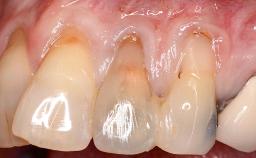

Connective-Tissue Graft to Increase the Width of the Keratinized Mucosa Around an Osseointegrated Implant

Adequate peri-implant soft-tissue thickness is essential not only for esthetic but also for functional reasons. In this case, Vincenzo Iorio Siciliano demonstrates how he achieved increased height and thickness of posterior peri-implant soft tissues to obtain a stable mucosal seal and a width of keratinized tissue favorable to toothbrushing.

The patient, a healthy 38-year-old woman, was referred for increasing the width of the keratinized tissues at the buccal aspect of dental implant 46. The site exhibited a premature-closure screw exposure caused by trauma during chewing, with inadequate keratinized tissue.